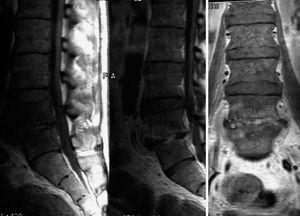

Así pues, una vez hubimos descartado un origen visceral del dolor tal y como se ha comentado previamente (lo cual era prioritario dado sus antecedentes de múltiple patología quirúrgica abdominal) y ante la imagen radiográfica que mostraba el paciente, se interpretó como un dolor lumbar de origen osteoarticular. Por todo ello, se realizó una resonancia magnética nuclear con el resultado de espacios y cuerpos vertebrales en L4-L5 hipointensos en T1, aumento de partes blandas anterior a dicho espacio y presencia de pequeños abscesos epidurales (fig. 1). Ante las características radiológicas mencionadas tanto de la radiografía simple de columna lumbar como de la resonancia magnética, se constató como causa del dolor la presencia de dicha imagen. La presencia de abscesos epidurales anteriores y las características descritas sugerían un origen infeccioso. Las metástasis o neoplasias que afectan a la columna vertebral suelen afectar más comúnmente al cuerpo vertebral que a los elementos posteriores, pueden adoptar aspecto de vértebra en marfil, que es típico del carcinoma de próstata, y en su evolución pueden afectar al pedículo de forma secundaria pero suelen respetar el espacio intervertebral. En lo que se refiere a la resonancia magnética nuclear, las metástasis suelen dar imágenes hipointensas en T1 mientras que en T2 suelen ser de intensidad más variable, aunque lo más característico es un aumento de la intensidad de la señal8. Ni la imagen ni la clínica de nuestro paciente parecía corresponder con un origen neoplásico.

Figura 1.Resonancia magnética nuclear en la que se observa destrucción del espacio intervertebral L4-L5, junto con aumento de partes blandas anterior a dicho espacio y presencia de pequeños abscesos epidurales.